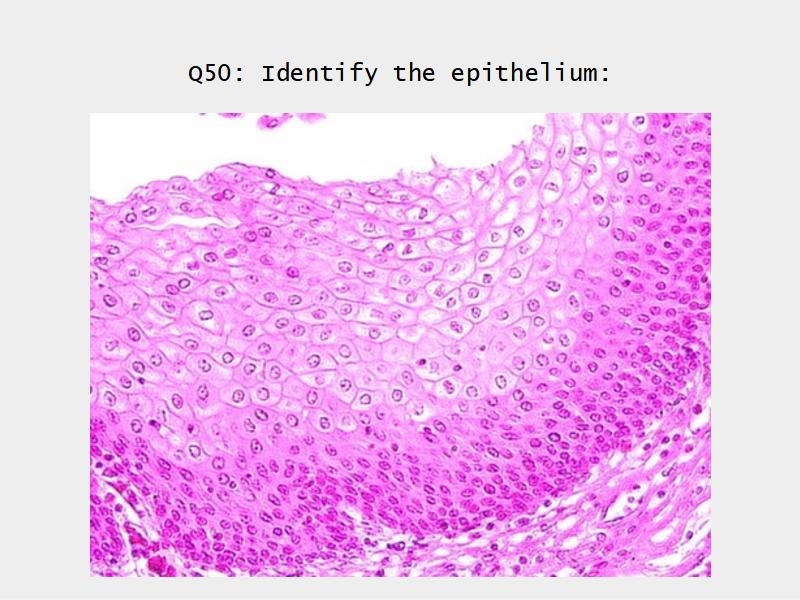

What cells are present?

Slides: Respiratory System

- Slide 71: Nostril

- Slide 72 & 74: Lung

- Slide 73: Trachea

- Slide 108: Olfactory epithelium

- Slide 111: Epiglottis